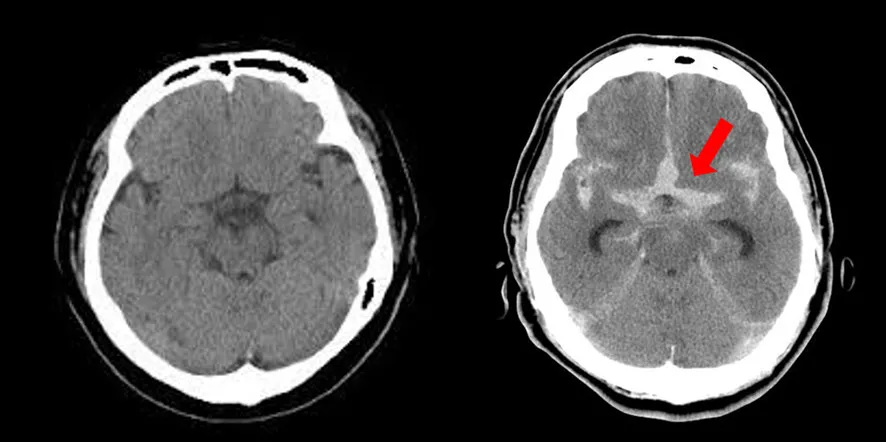

我看了PPT,是一個病例分析,老年女性,突發頭痛,伴有噁心嘔吐症狀,然後做了急診頭顱CT。

蛛網膜下腔出血:腦室高信號

我一看,好傢伙,這腦室都是高密度信號,結合症狀, 是典型的蛛網膜下腔出血。

“病人的診斷考慮是?”老師問道。

**“蛛血!”**我終於遇到一道自己有把握的題目了,興奮地説出了口。

“你沒在腦外科輪轉過?我怎麼不信呢?”

萬萬沒想到,一句蛛血暴露了自己。蛛血是腦外科、神經內科醫生們對蛛網膜下腔出血的簡稱,沒輪轉過的醫生,確實很少直接這樣簡稱。我也是聽腦外科的老師們這麼説,自己才記住的。